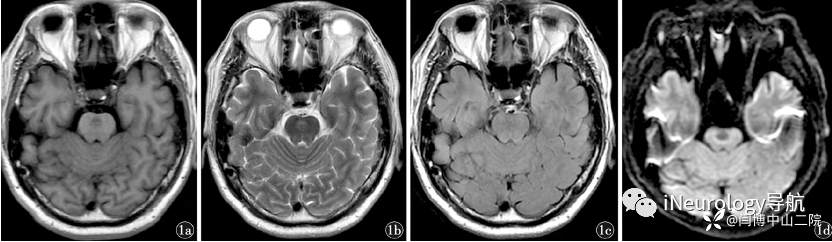

我遇到一个头晕的患者,病变在桥脑,做过3次头部核磁共振,按照脱髓鞘疾病进行治疗,药物也是服用过很多,症状时好时坏。片子见下图。

这个就是脑桥毛细血管扩张症,这个病变长期稳定无进展,如果不懂就导致不断的复查治疗效果,核磁共振片子做个不停。